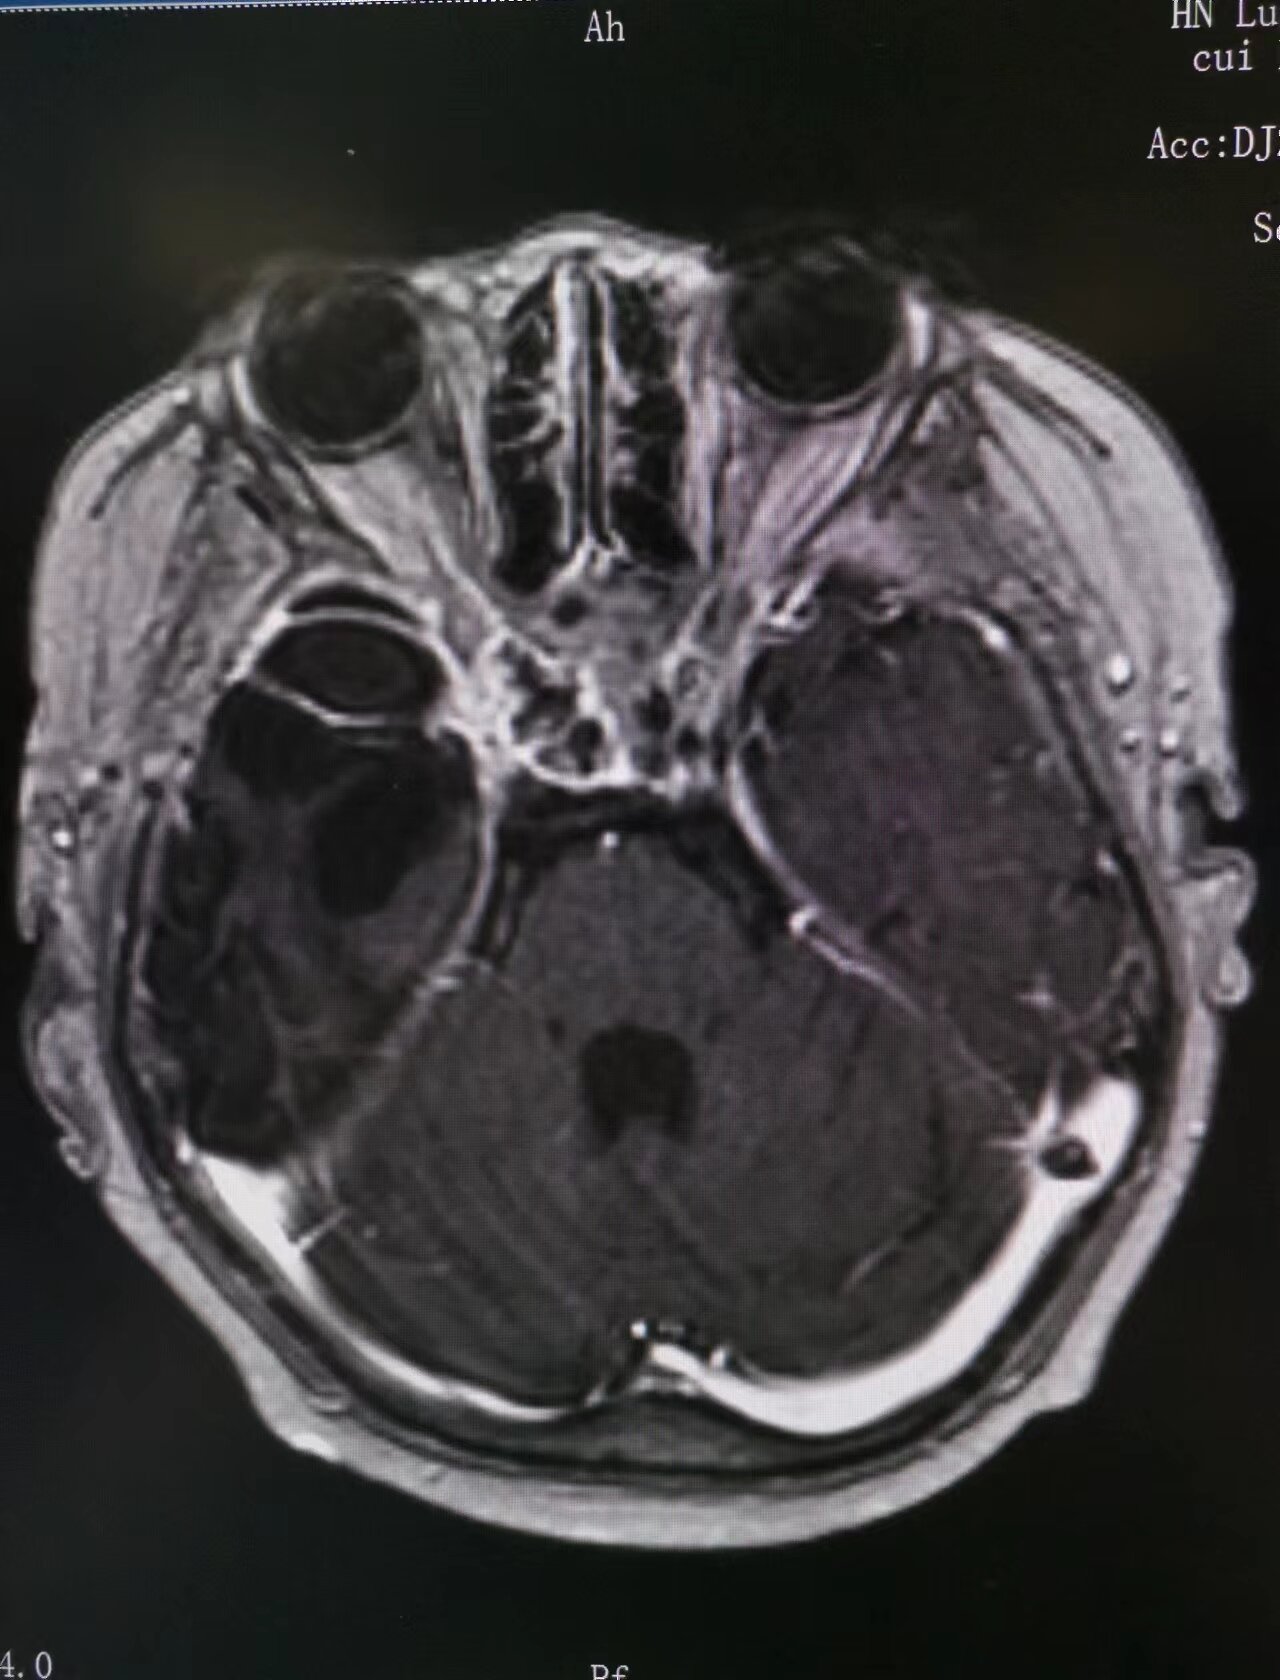

14歲的強(qiáng)強(qiáng),在2018年9歲時(shí)因鞍區(qū)顱咽管瘤(造釉細(xì)胞型)占位壓迫視神經(jīng)導(dǎo)致右眼失明,且合并多發(fā)垂體功能紊亂,家長帶患兒反復(fù)輾轉(zhuǎn)北京多家知名醫(yī)院診治。2022年9月的一天,患兒左眼忽然失明,再次赴京診治,考慮鞍區(qū)腫瘤局部壓迫導(dǎo)致孩子的病情急劇加重,但是因腫瘤與頸內(nèi)動(dòng)脈、右側(cè)大腦中動(dòng)脈及下丘腦等周圍重要器官及組織黏連緊密,手術(shù)風(fēng)險(xiǎn)大,只能進(jìn)行部分切除。術(shù)后患兒出現(xiàn)腦梗塞及左側(cè)肢體偏癱,間斷復(fù)查。2023年2月,患兒腦梗塞恢復(fù)后,為尋求進(jìn)一步診治,家長及患兒慕名來到市二院放療科就診。

市二院放療科主任趙亮接診后,帶領(lǐng)科室團(tuán)隊(duì)迅速評(píng)估患兒病情,發(fā)現(xiàn)強(qiáng)強(qiáng)顱咽管瘤術(shù)后腫瘤殘存,鞍區(qū)占位緊鄰腦干與視神經(jīng)、視交叉分界不清,雙眼失明、左側(cè)肌力下降,發(fā)育遲緩?;純翰∏閺?fù)雜,趙亮主任立即匯報(bào)醫(yī)務(wù)科,由醫(yī)務(wù)科組織全院多學(xué)科會(huì)診(MDT),邀請影像科、神經(jīng)內(nèi)科、神經(jīng)外科、小兒內(nèi)分泌科、腫瘤內(nèi)科等相關(guān)科室專家會(huì)診討論,參考診療規(guī)范及國內(nèi)外文獻(xiàn),結(jié)合放療科三維放療技術(shù)優(yōu)勢,考慮到患兒年齡小,三維適型調(diào)強(qiáng)放療對接近關(guān)鍵結(jié)構(gòu)的不規(guī)則形狀腫瘤具有高度靶向一致性,同時(shí)能最大限度減少對周圍正常組織輻射照射等技術(shù)優(yōu)勢,趙亮主任與患兒及家屬充分溝通,制定了以三維適型調(diào)強(qiáng)放射治療為主的綜合治療方案。